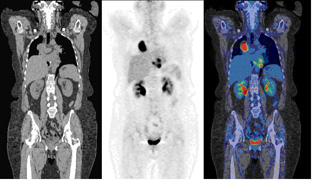

PET/CT Clínico

PET/CT Clínico,? Flujo de trabajo y protocolos clínicos,? Artefactos y Variantes Normales?